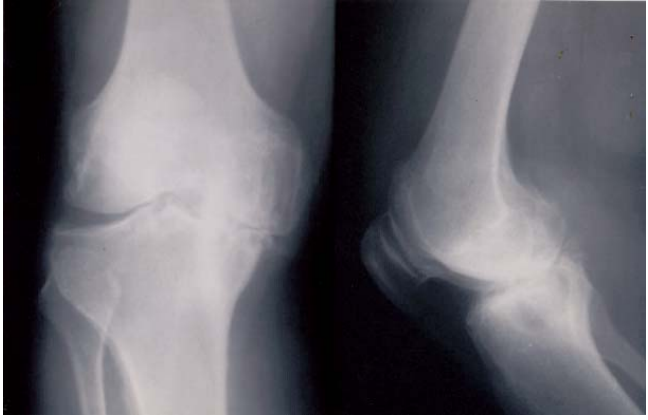

32 一位 24 歲男性的右手腕關節疼痛腫脹有二個月之久。他本人不記得右手有受傷過,經服用消炎片雖 有止痛效果,但是該關節越來越惡化而無法彎曲。X 光檢查如附圖。抽取關節液檢查發現:WBC105000/μL、glucose<20 mg/dL,顯微鏡觀察無結晶物發現。最適切的診斷為何?

(A) Rheumatoid arthritis (B)Calcium pyrophosphate dihydrate deposition disease (C)Infectious arthritis (D)Complex regional pain syndrome